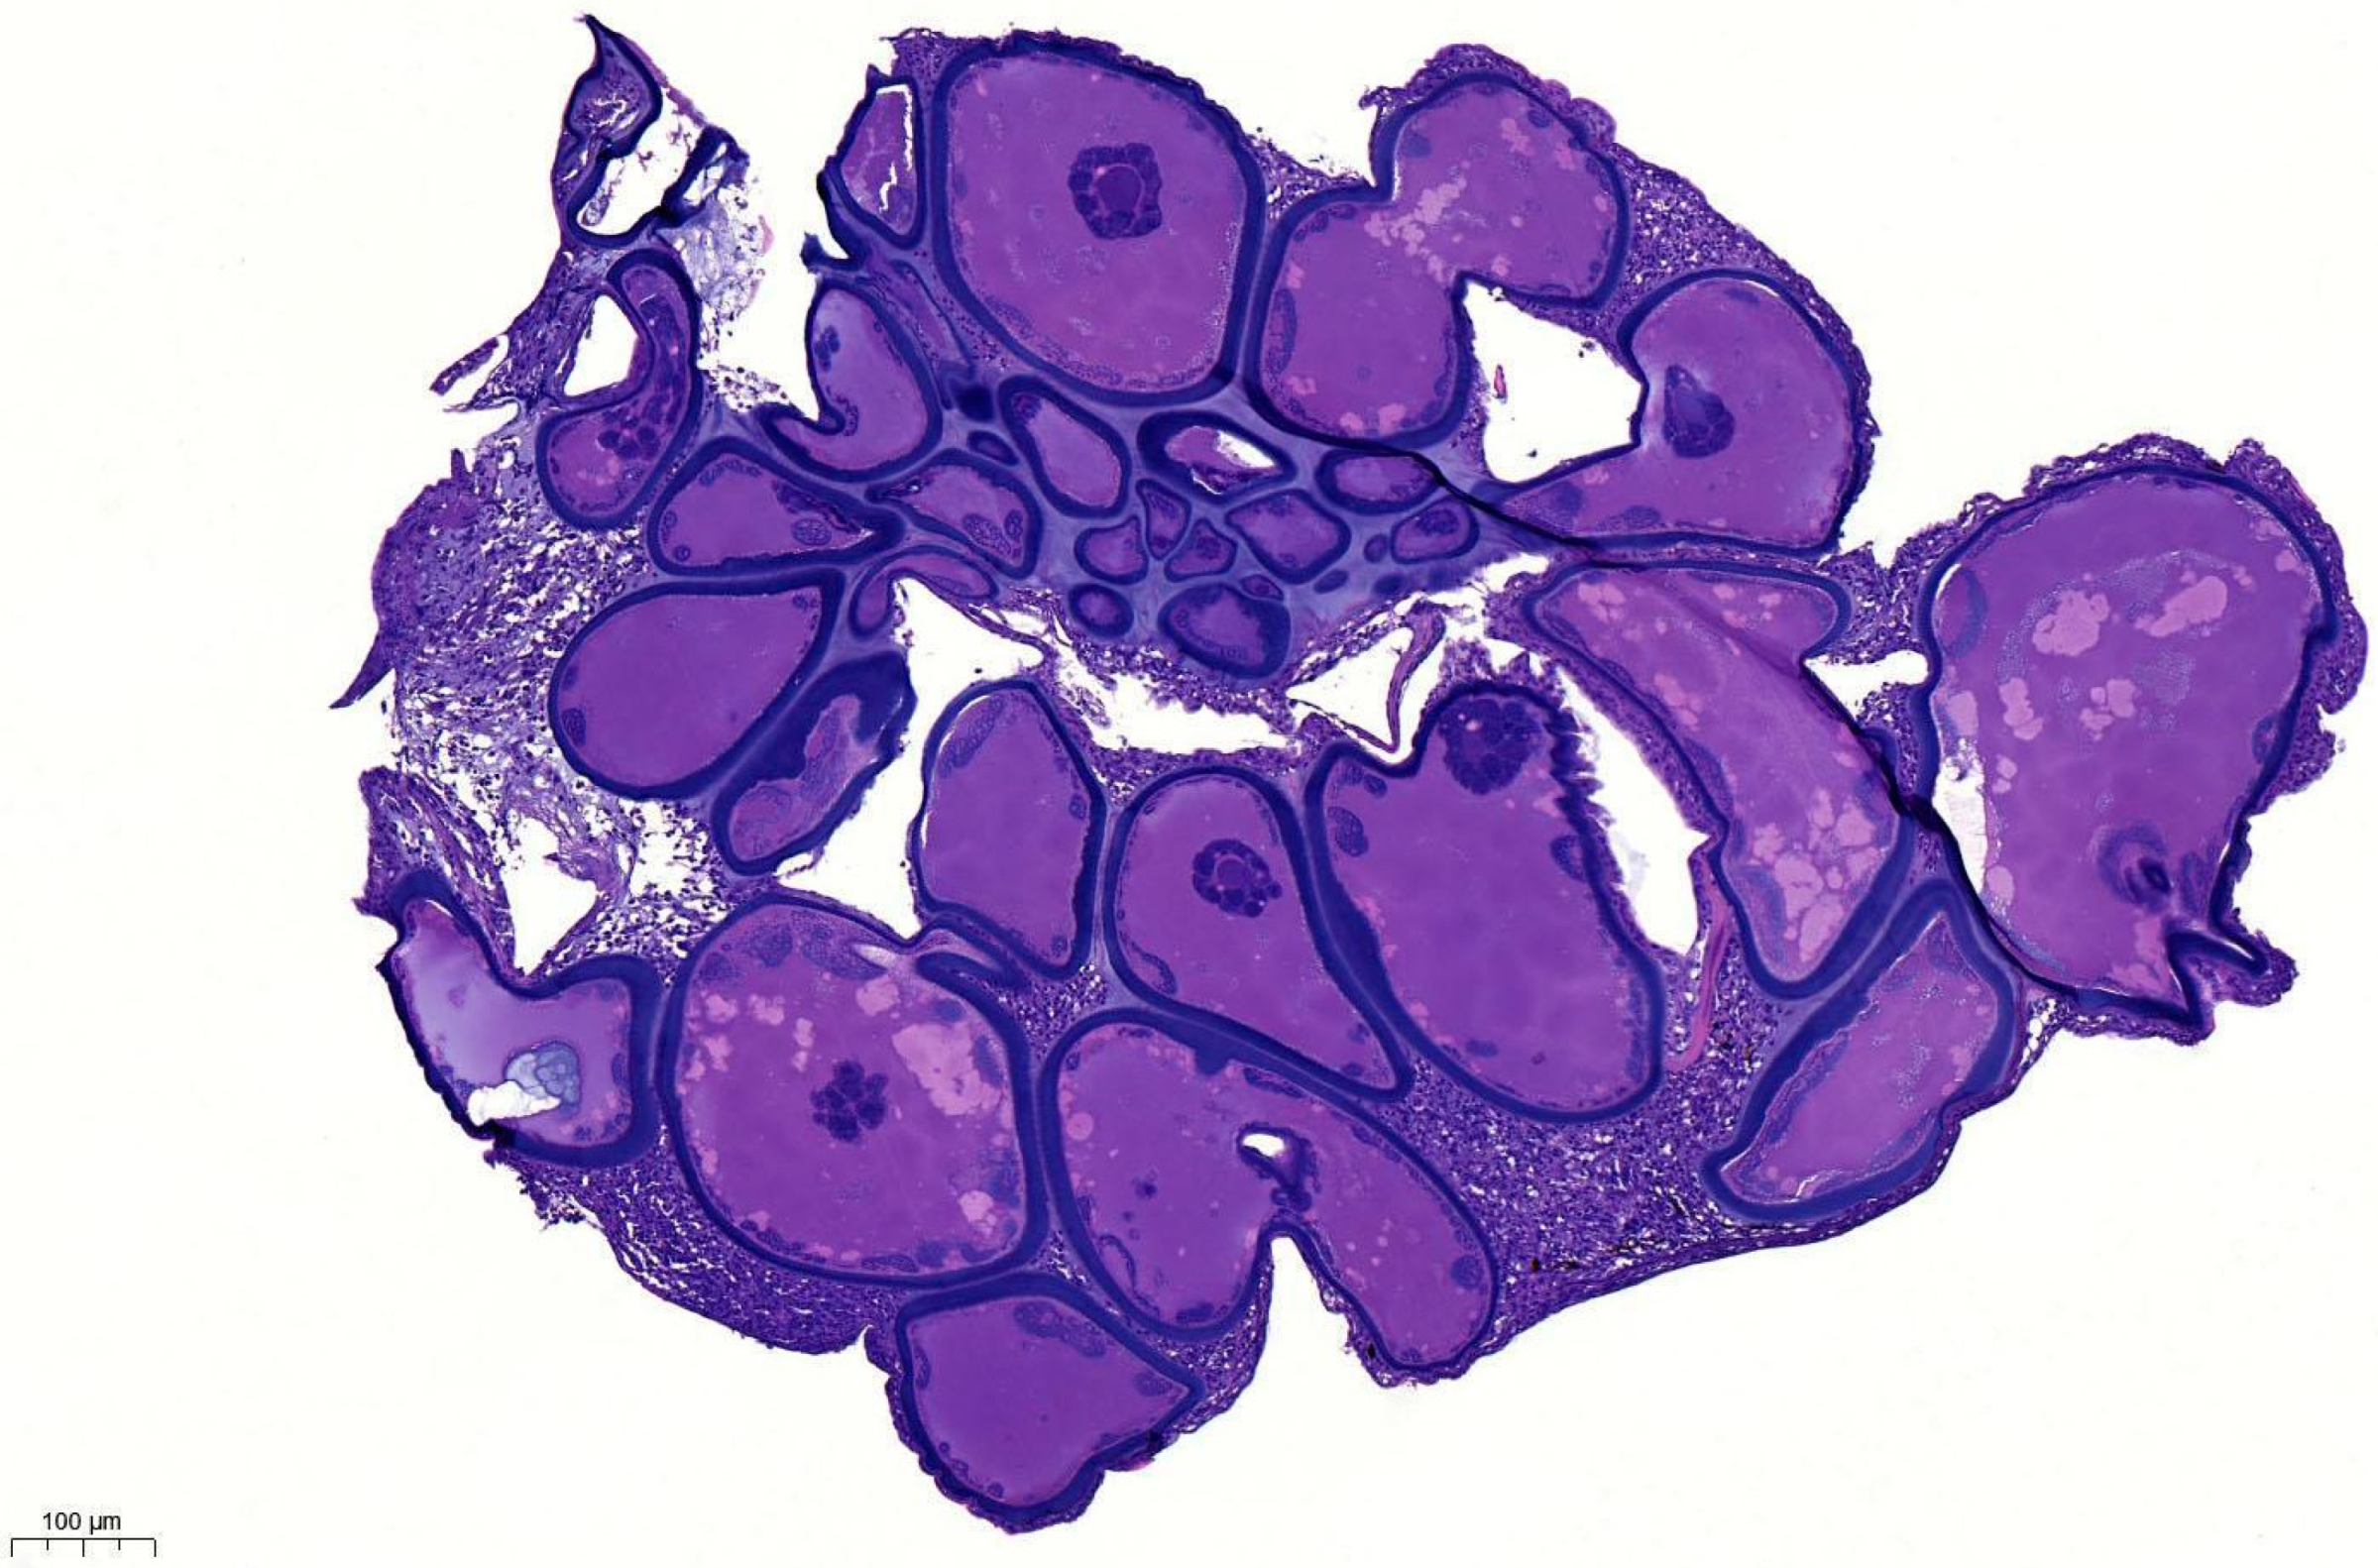

3.1. Histopathology